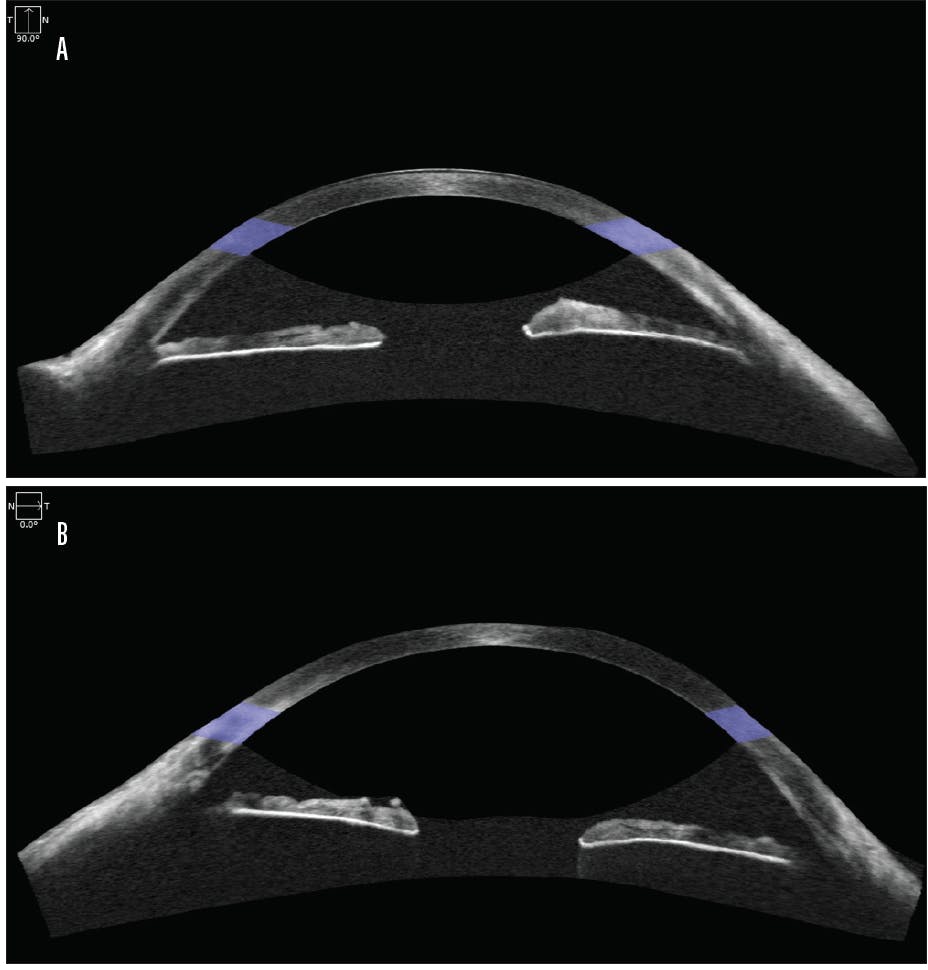

Treatment was initiated. The patient’s routine postoperative steroid regimen was reduced, and twice-daily atropine therapy was started. At 3 weeks postoperatively, the anterior chamber had shallowed further, and IOP was 2 mm Hg. BCVA was 20/25, and no hypotony maculopathy was present. Repeat imaging with AS-OCT revealed a reduced cleft size (35º) and effusion height (493 μm; Figure 3). Conservative management was therefore continued.

Figure 3. At 3 weeks after GATT, AS-OCT revealed a reduced cleft size (35º) and effusion height (493 µm).

Courtesy of Thomas A. Berk, MD, and Hady Saheb, MD, MPH, FRCSC